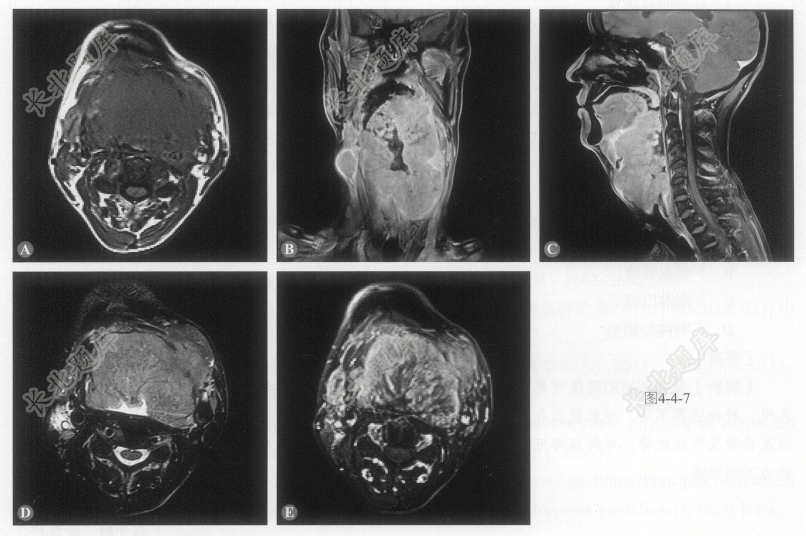

患者男性,45岁,因声音嘶哑2个月就诊。MRI检查如图4-4-7。

- 多项选择题2.在提供的MRI图像上,病灶可能累及的部位有:

A、口咽双侧壁

B、双侧舌根部

C、左侧咽旁间隙

D、双侧会厌前间隙

- 多项选择题3.该病例中有助于提示恶性的MRI征象有:

A、骨质明显破坏

B、边界模糊,与邻近组织分界不清

C、颈部淋巴结肿大

D、增强扫描呈不均匀强化

- 多项选择题4.该病例最有可能诊断为:

A、下咽鳞癌

B、下咽血管瘤

C、下咽淋巴瘤

D、下咽神经鞘瘤